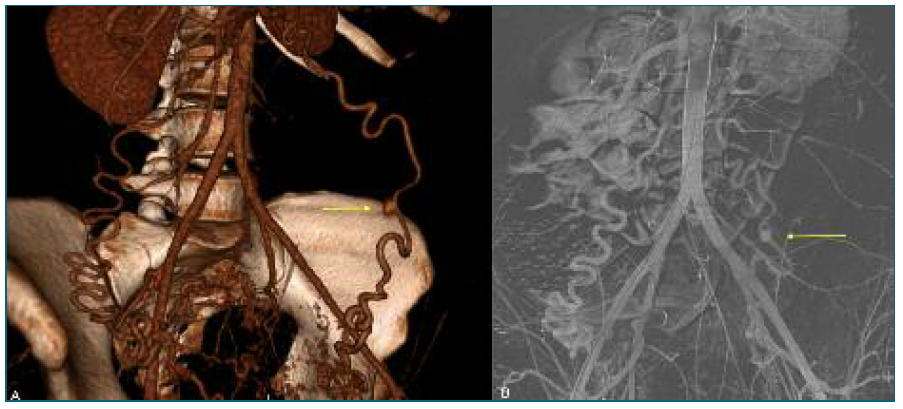

Initial laboratory tests revealed a hemoglobin drop from 11 g/dL in late pregnancy to 9.3 g/dL, suggesting mild postpartum anemia. A renal-bladder ultrasound and an abdominal X-ray imaging (Figure 1) were performed, excluding urinary and intestinal complications. Persistent pain along with an episode of lipothymia prompted an urgent abdominopelvic contrast-enhanced CT-scan, revealing a 19 cm retroperitoneal hematoma in the left flank and iliac fossa (Figure 2). Additionally, a 7 mm pseudoaneurysm in the LOA was identified as the source of intermittent hemorrhage (Figure 3A).

Figure 2 Abdominal-pelvic CT scan performed 2 days postpartum, showing a retroperitoneal hematoma measuring at least 12 × 13.4 × 19 cm (anteroposterior × transverse × longitudinal), localized in the left flank and iliac fossa. An enlarged uterus with a heterogeneous enhancement pattern results from normal postpartum changes.

Figure 3 (A) Three-dimensional CT scan reconstruction showing a 7 mm saccular structure in the LOA, consistent with an ovarian artery pseudoaneurysm. No active bleeding was observed at the time of image acquisition, though intermittent hemorrhage was suspected; (B) Diagnostic angiography confirming the OAA in the LOA with active bleeding proximally to the pseudoaneurysm. The yellow arrows represent the OAA identified in both imaging diagnostic tools.

Hemoglobin dropped to 5.2 g/dL within a few hours, and the patient was transferred to the ICU to immediate resuscitation with 1 L crystalloid, 1 gram of tranexamic acid, and 3 units of red blood cells. After consultation with the vascular surgical team, the patient was taken to the Angio-Suite for urgent TAE. Approaching the common femoral artery, the LOA was selectively catheterized, and a diagnostic angiography confirmed the pseudoaneurysm (Figure 3B), with active bleeding at its proximal segment. Embolization of the proximal LOA was performed with 3.0- and 4.0-mm micro-coils. In attempting to microcatheterize the distal LOA, a new bleeding episode was identified, requiring additional embolization with thrombin and a 6.0-mm micro-coil (Figure 4A). Post-embolization angiography of the left hypogastric and common iliac arteries confirmed successful occlusion of LOA. (Figure 4B). Post-TAE, the patient was transfused an additional unit of erythrocytes, achieving a hemoglobin level of 8.5 g/dL. The patient had an uneventful recovery and was discharged within 5 days.

Figure 4 (A) Using a Cobra catheter via the common femoral artery, the proximal segment of the LOA was accessed and embolization with micro-coil was performed (MReye® coils, 3.0- and 4.0-mm). Due to contrast leakage after catheterization of the distal LOA, additional embolization with thrombin and a 6.0-mm micro-coil was performed. (B) Post-embolization control angiography through the left hypogastric and left common iliac arteries showed no evidence of active bleeding, confirming successful occlusion of the LOA.

By the 4th week postpartum, the patient presented a normal-ranged hemoglobin level (12.1 g/dL) with a normal physical examination. The patient underwent a multidisciplinary follow-up which included gynecology, internal medicine, genetics, and vascular surgery. At 6 months postpartum, a Next Generation Sequencing panel ruled out any causal variants of connective tissue disorders. Sequential CT-scans revealed retroperitoneal hematoma regression from 97 mm to 52 mm at 3 and 8 months postpartum, with complete resolution by 23 months (Figure 5). The patient remains under gynecological follow-up, being asymptomatic since post-TAE discharge.

Figure 5 Complete spontaneous resolution of the retroperitoneal hematoma after 23 months of postpartum and post-TAE, with neither early nor long-term complications reported.